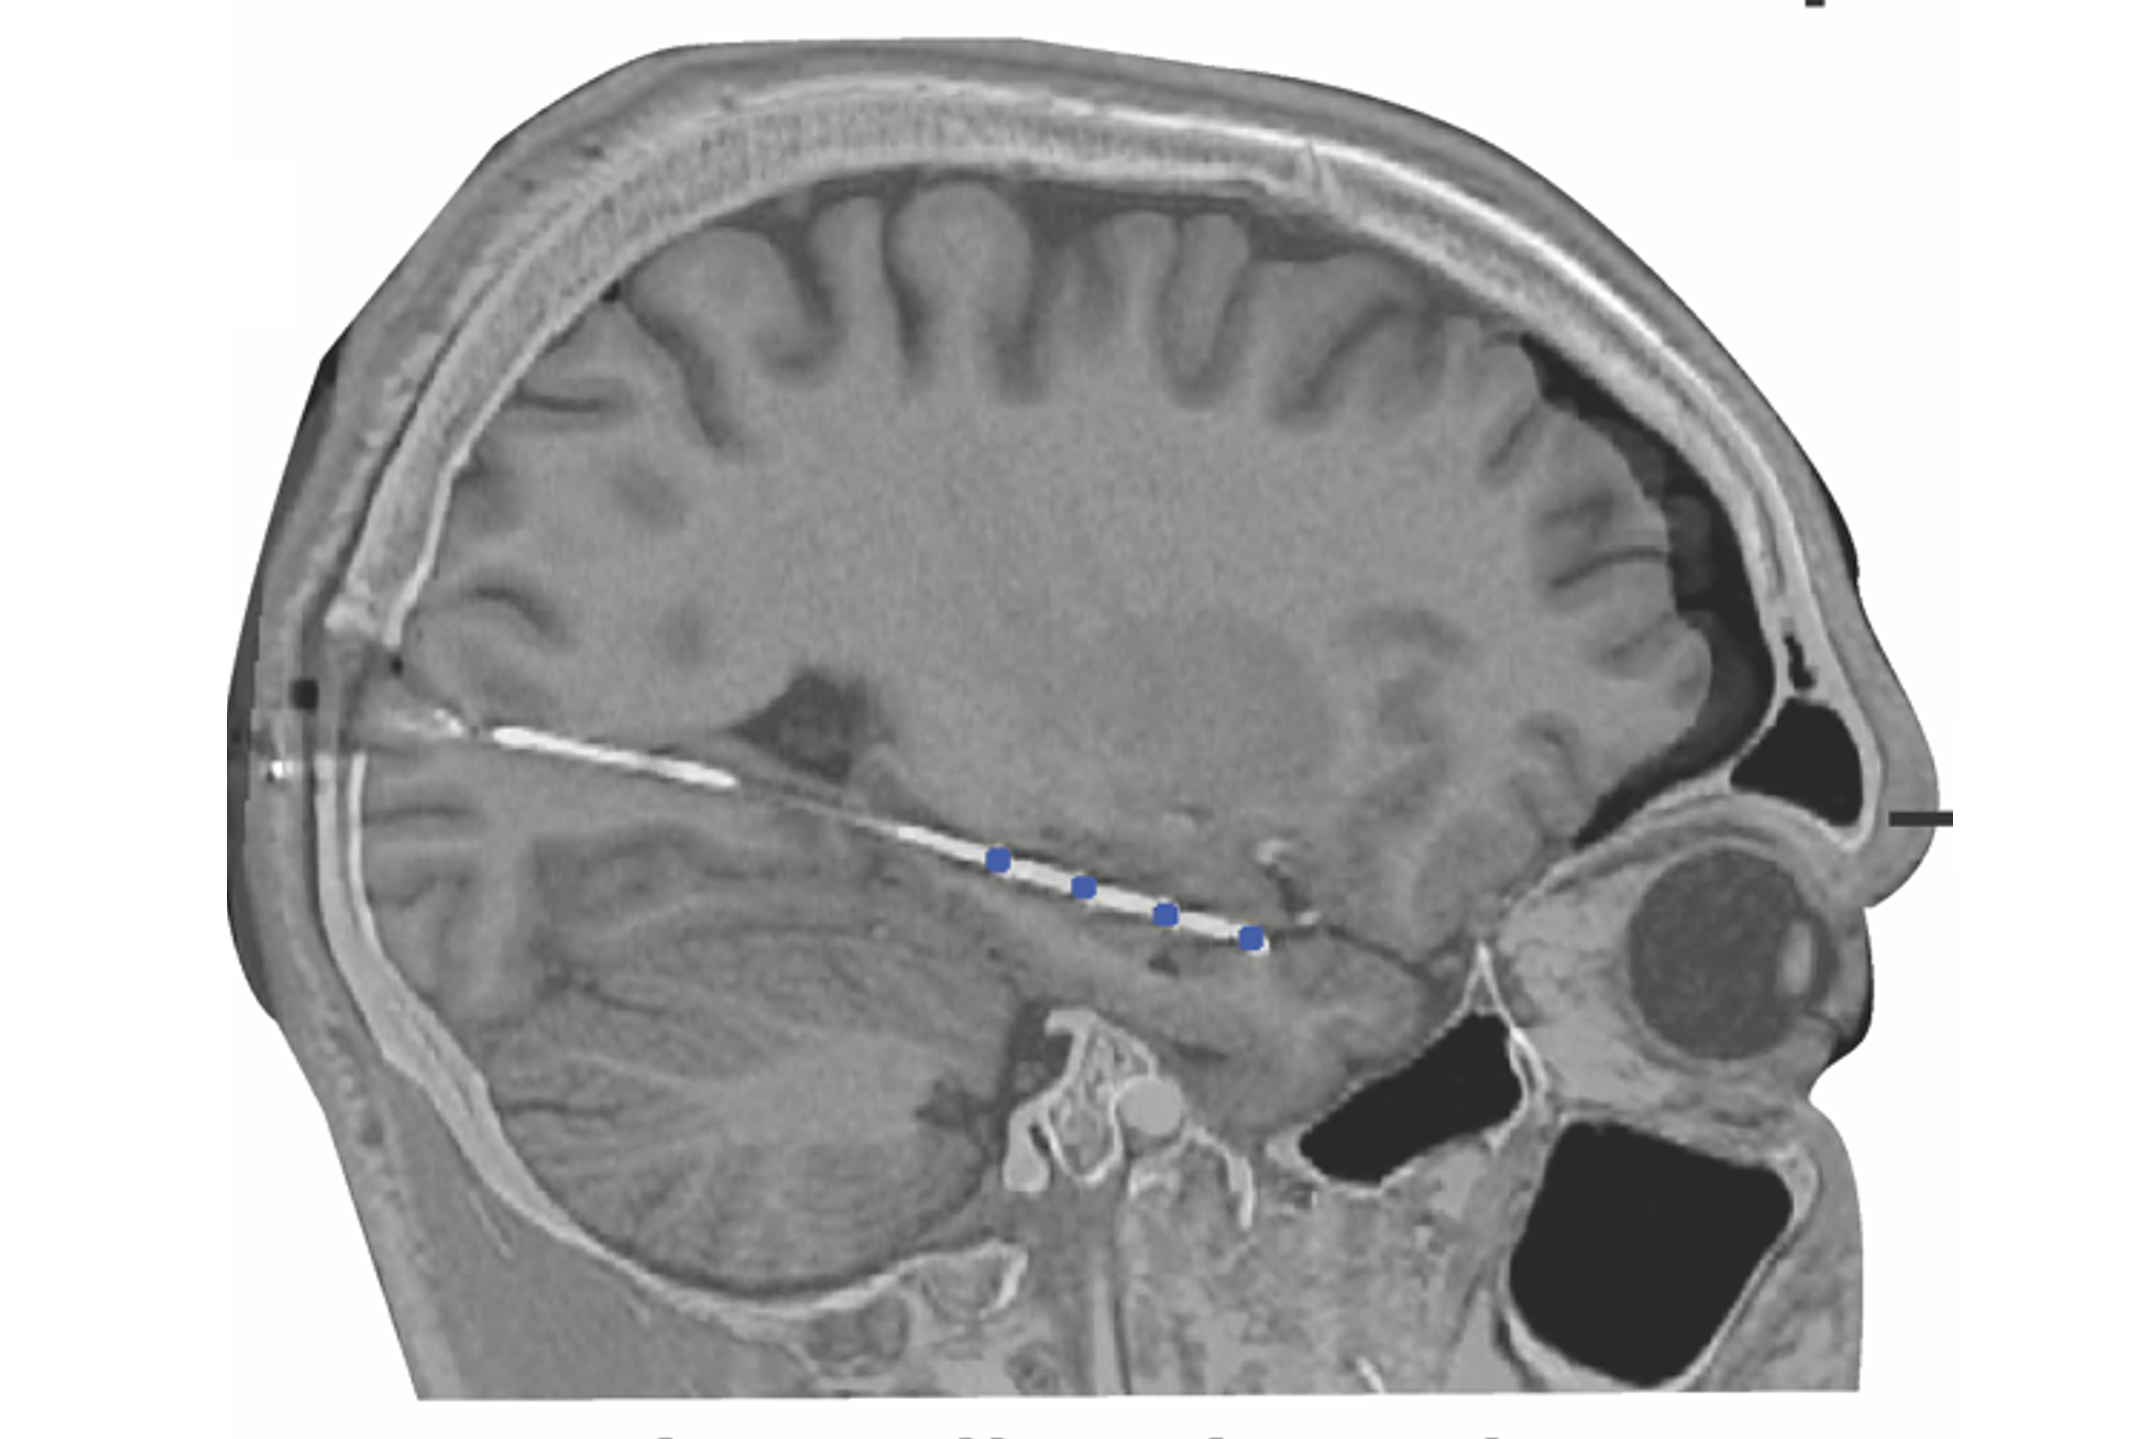

Next Generation Neural Interfacing

Future neural interfaces will include minimally-invasive and bidirectional systems. We are helping to develop implants, wearables, and remote devices that leverage computational models and real-time human-to-device communication to enable brain-based control and alleviate neurological symptoms.